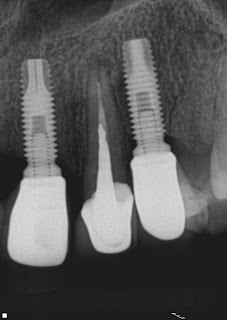

Segue documentação de tratamento realizado esta tarde no dente 22 em sessão única.

Para a resolução desse caso, os seguintes procedimentos foram realizados:

- Moldagem inicial com silicona de condensação

- Remoção da coroa total

- Remoção do NMF

- Preparo da base do núcleo: http://youtu.be/KVxtenSFD1c

- Remoção no retentor pela técnica SISU: http://www.youtube.com/watch?v=Er94SZ9n4hY

- Retratamento endodôntico(desobturação com ultrassom; repreparo com ampliação foraminal e uso de gel de clorexidina a 2% como substância química auxiliar)

- Obturação com MTA devido ao formato ovalado do forame apical

- Instalação de pino de fibra de vidro

- Confecção de núcleo de preenchimento em resina composta

- Confecção de coroa provisória com Protemp